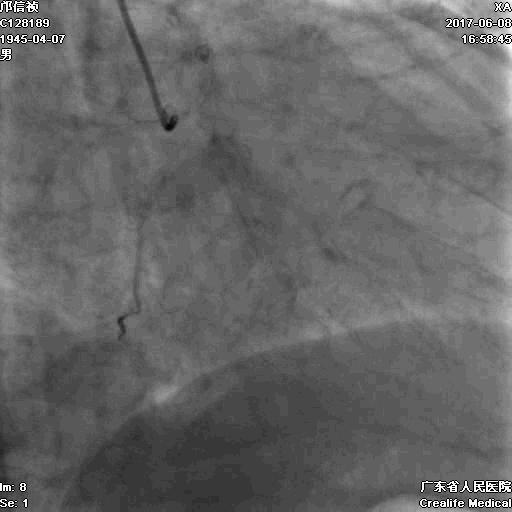

首先:IVUS指导下干预LAD

4.0mm*13mm药物支架